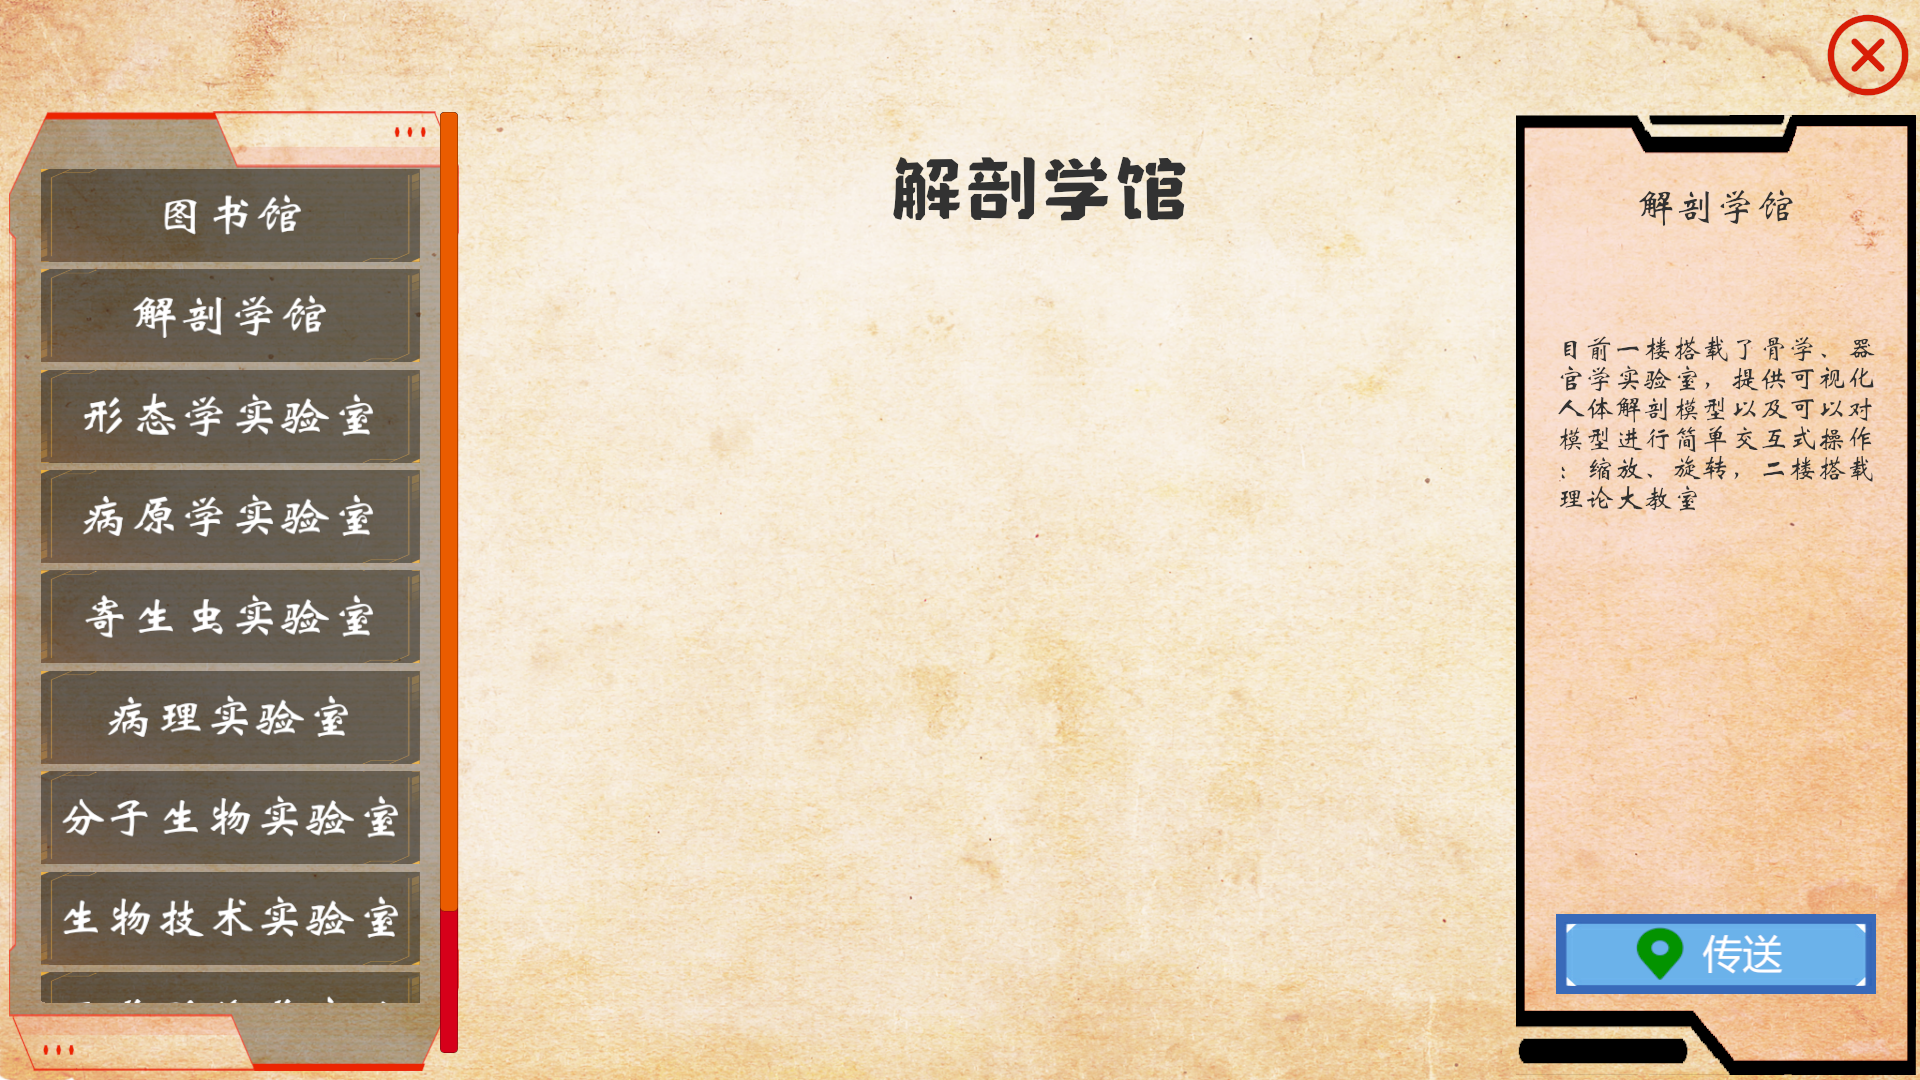

本产品打破以往产品功能单一的局面,目前具有解剖教学、组胚教学、影像教学、模拟介入手术等功能

解剖教学模块内置了人体全骨骼标本,你可以根据系统索引进行学习

组胚教学模块内置了人体组织学与胚胎学常见光镜切片标本,您可以随时访问这些资源

影像学模块模拟PAC系统,在这里您可以学习到各种疾病的影像学表现

基于DICOM影像数据生成病例模型,这里您可以体会介入手术的方式

以下是产品内截图实况